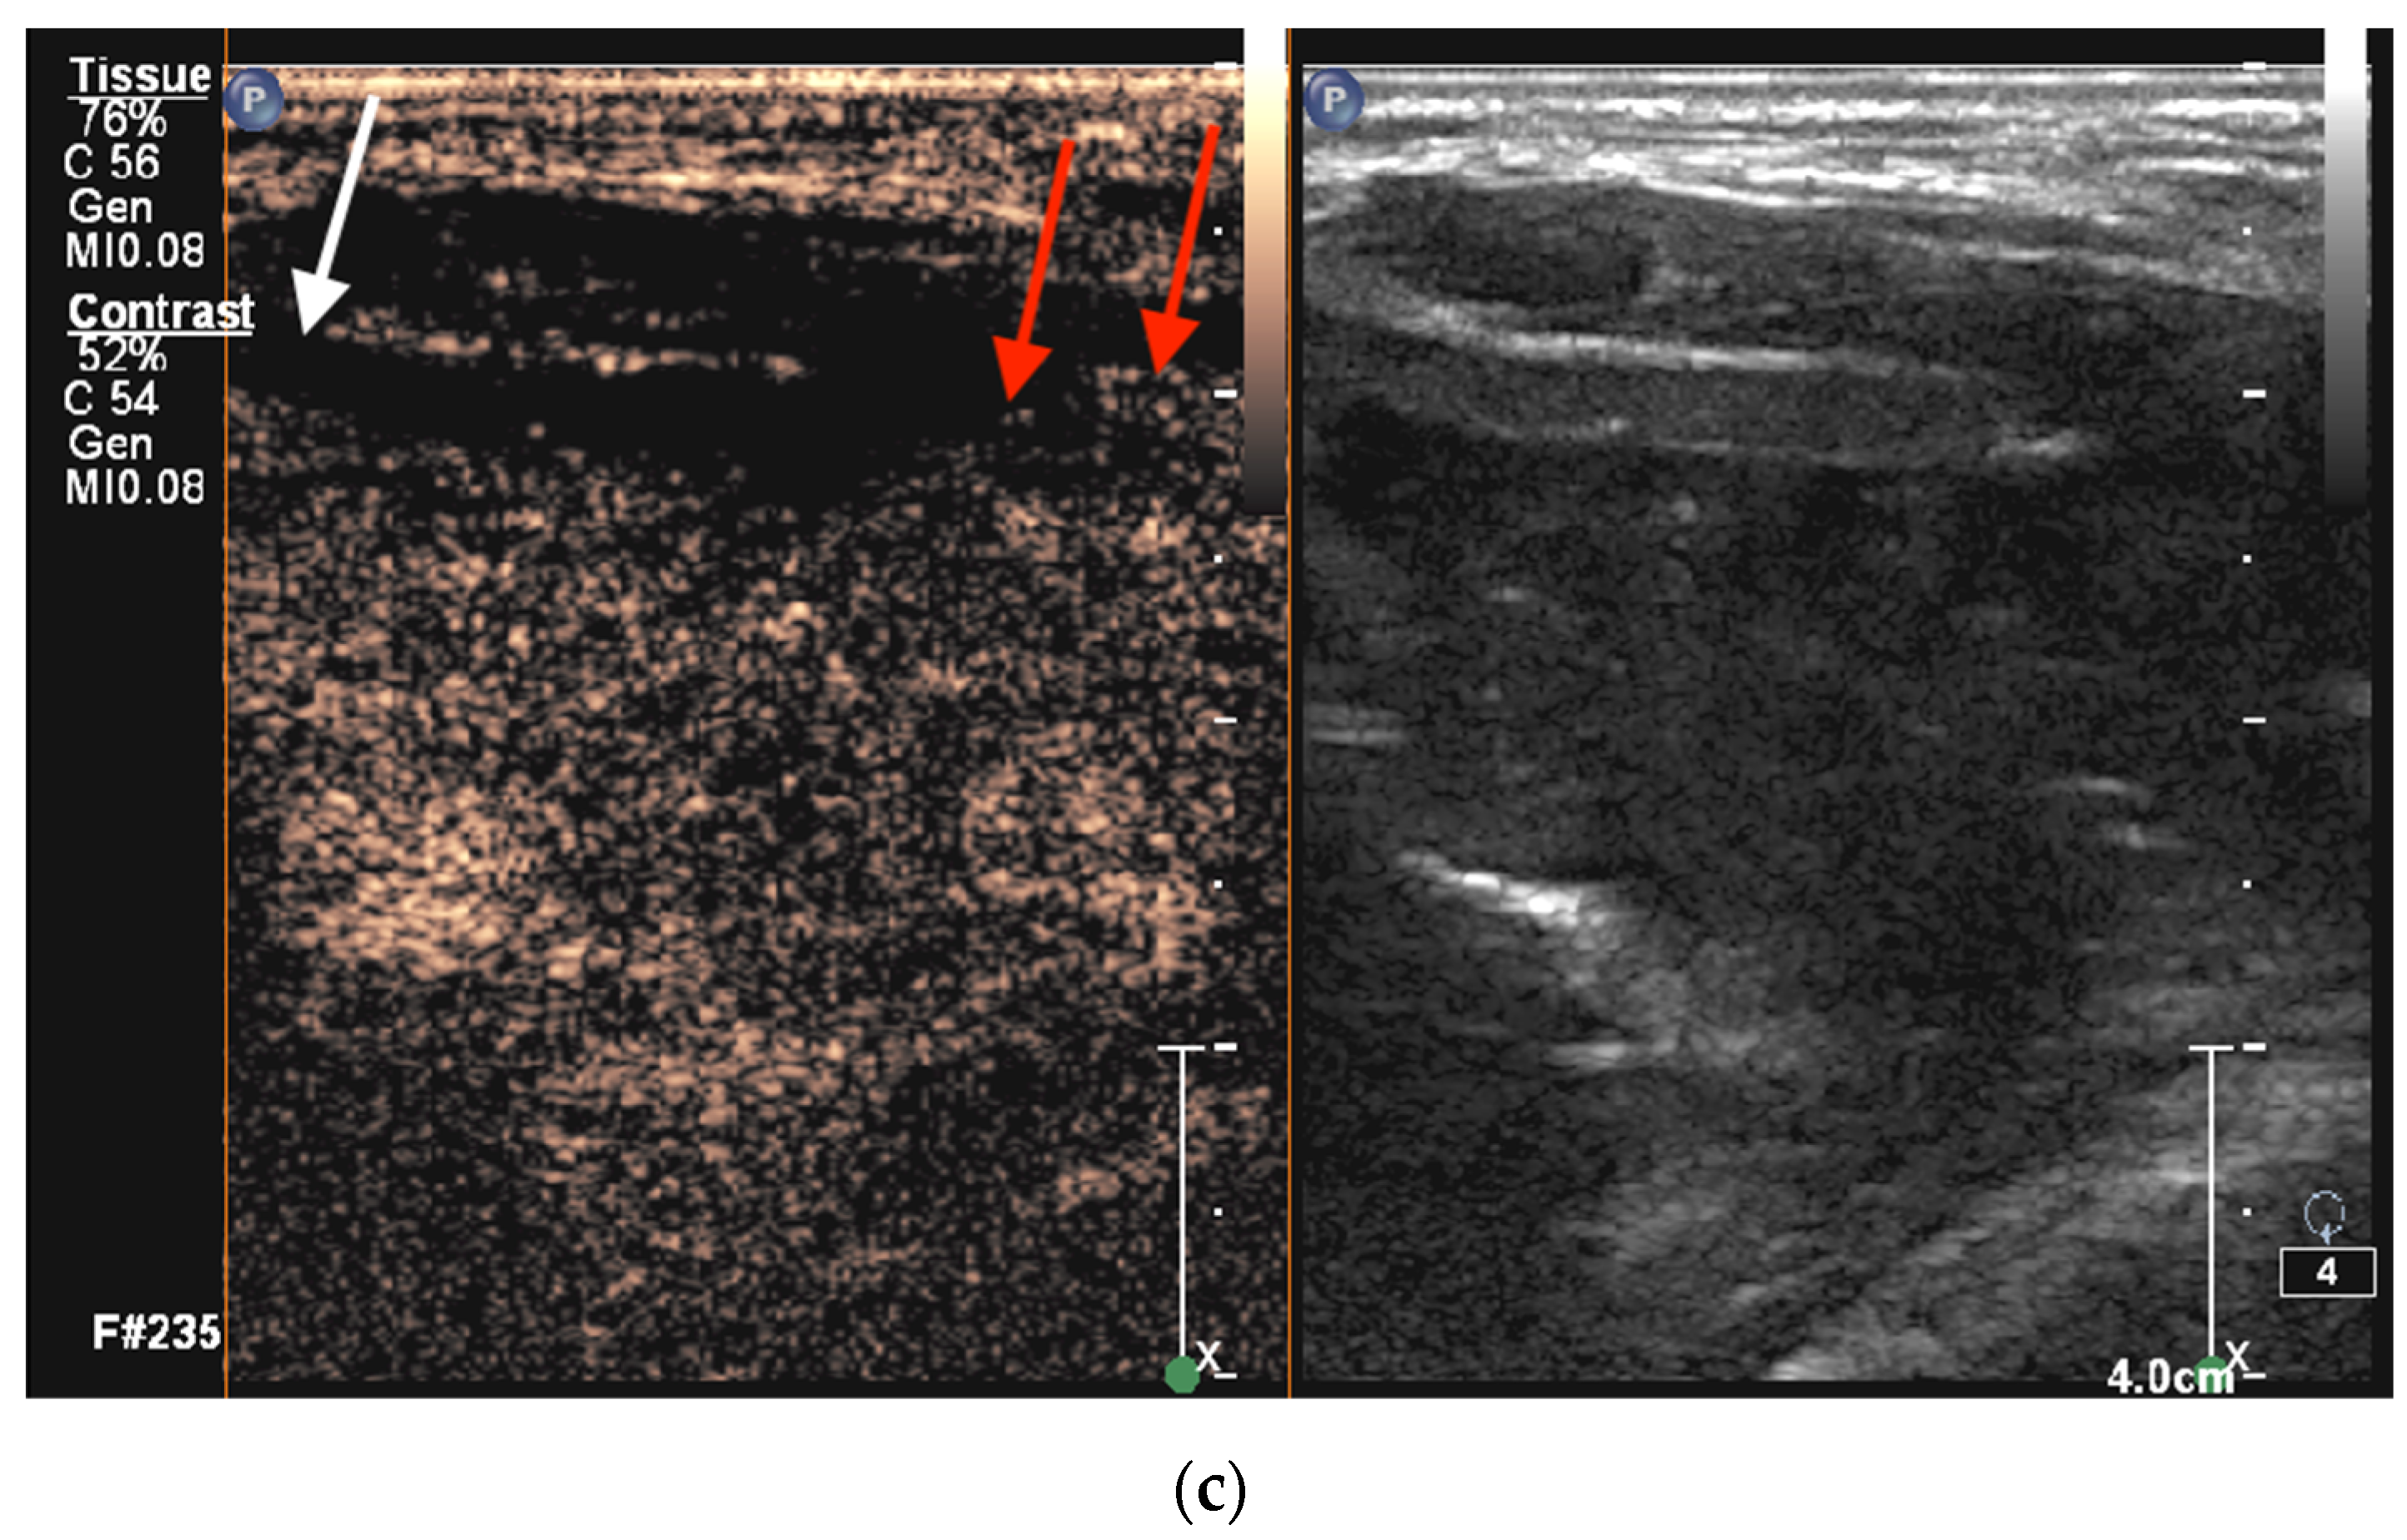

2.5.1. CEUS Imaging

2.5.2. Cross-Sectional Imaging